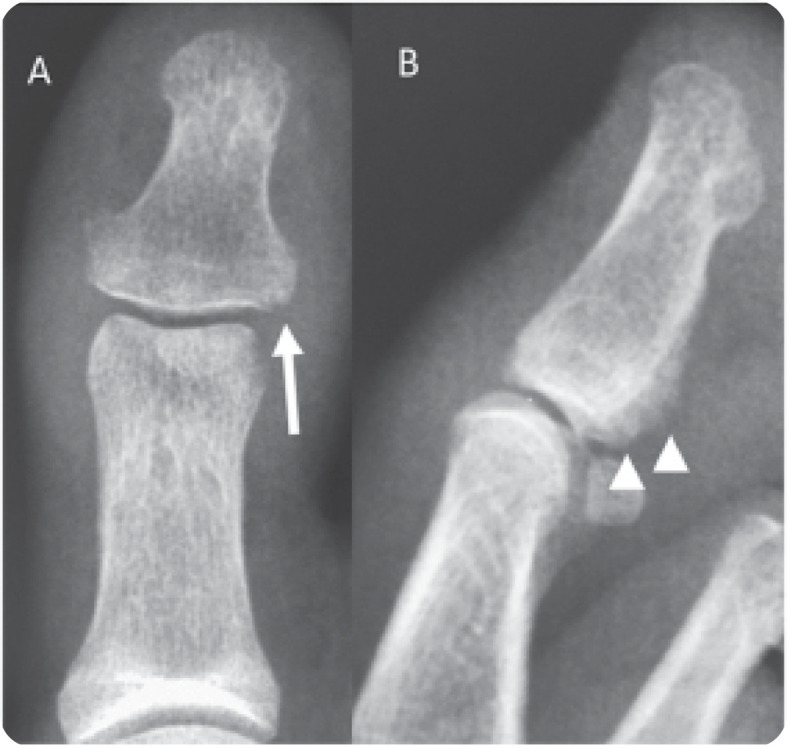

Psoriatic Onycho-Pachydermo Periostitis (POPP).